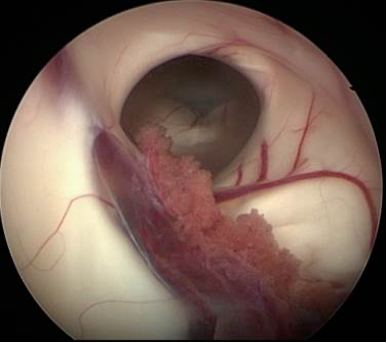

Karl Storz, beyin cerrahisi ürün yelpazesinde bulunan Little Lotta seti ile pediatrik veya dar foramene sahip hastalara, Endoskopik Üçüncü Ventrikülostomi yapmak ve/veya biyopsi almak mümkündür.

- Mükemmel anatomik görüntü